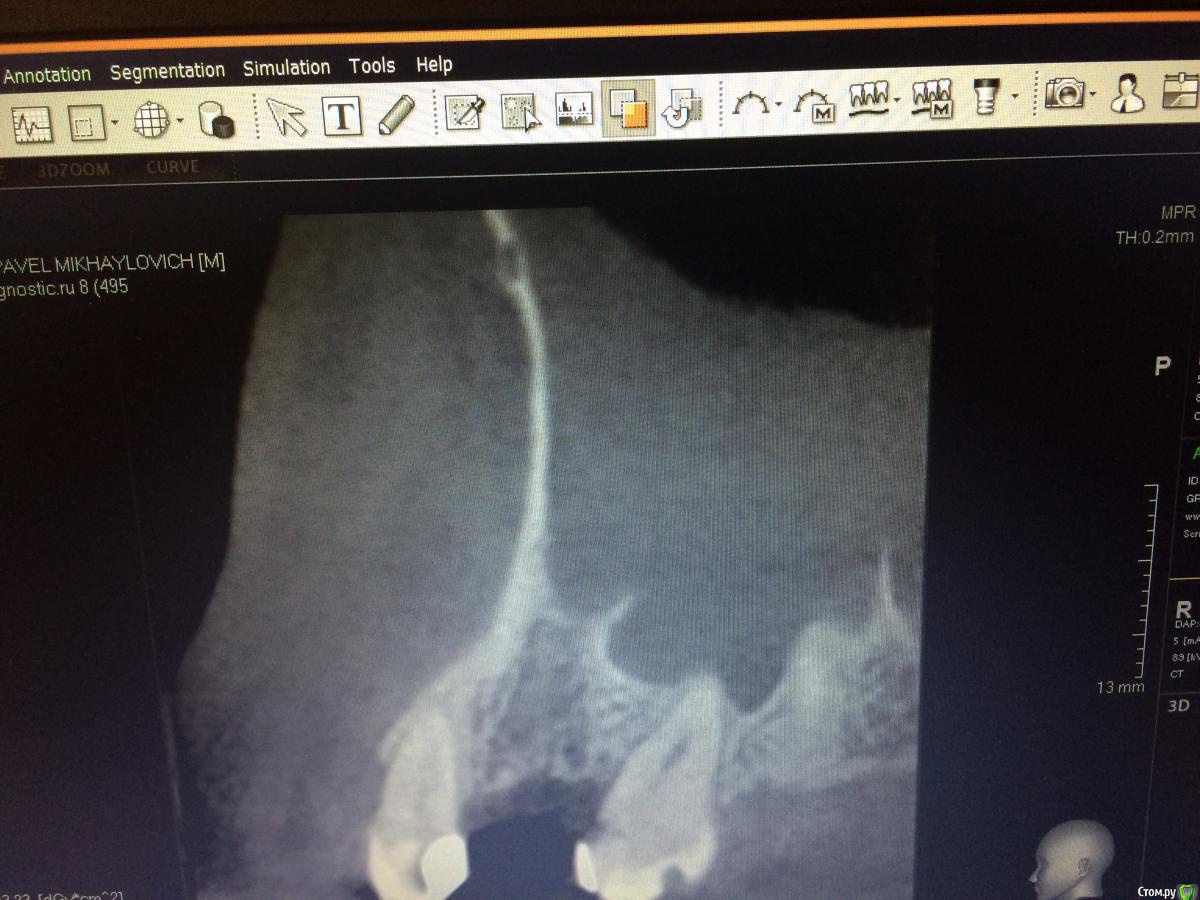

Graffwoman Опубликовано 25 февраля, 2018 Автор Поделиться Опубликовано 25 февраля, 2018 (изменено) внесу свою лепту Сосудосуживающий капли в нос на 10 дней - в каждый носовой ход Амоксиклав 1000 мг по 1 2 рд 5 дней либо супракс либо таваник - их легче принимать Бифиформ АциполНимесил 100 мг по 1 пакет 2 рд 7 дней Хлоргексидин или мирамистин - ротовые ванночки до 6 раз в день, потом сразу солкосерил дентальный наносить - он держится намного лучше других гелей и паст ,хватает трех раз в день Ну ,вообщем, это стандартный набор Из протокола хотел выяснить 1. чем сверлились ? был ли использован набор для закрытого синуса ?2. когда удаляли ( если это были Вы ) качественно ли был выполнен корежат?3.торк ?не вижу смысла трогать имплантат сейчас .Пусть заживает вторичным натяжением .Приживется - хорошо ,нет - переставите .Спасибо1.Стандартный набор Osstem2.Хороший вопрос.Прошло 1,5 года с момента удаления.Причину удаления сходу не вспомню ,но процесс был хроническим,без признаков воспаления.На верхушке корня после удаления была прикрепленная гранулема. .Кюретаж был ,как считали тогда- легкий (гранулема то вышла ),но качественный.Проба на соустье после удаления отрицательная.Сгусток формировался слабо,в лунку рыхло положила губку с йодоформом. Неожиданно лунка заживала плохо,вялотекущий альвеолит. Дополнительный неагрессивный кюретаж и промывание ХГ. .Но.... Через год- КТ и поняли,что кость не полноценная. На слизистой десны вроде легкое углубление-точка. Не придали значения,может,ревизию надо было сделать??? .Больше насторожил обьем слизистой в пазухе-до 25 мм,на сегодня -до 10). Долго ходил по ЛОРам -толку никакого. Решили оставить в надежде,может кость сформируется.,теперь снова вернулись.Всю остальную историю уже знаете. Прилагаю снимок первого КТ, по поводу размытой границы гайморовой -ничего пока не могу сказать,кажется,это просто такой ракурс. .3.Торк 45Сейчас принимает ципрофлоксацин третьи сутки по 500 мг 2р/д,антигистаминные, нимесил получается 2р/д,(тк к вечеру стал ныть снова),противогрибковые и для флоры кишечника. Как думаете ,а боль в проекции верхушки имлантата -откуда ? Изменено 25 февраля, 2018 пользователем Graffwoman Ссылка на комментарий

rytovst Опубликовано 26 февраля, 2018 Поделиться Опубликовано 26 февраля, 2018 боли одного характера ,одинаковой силы ?возможно была перфорация при удалении - трудно судить / много времени прошло вначале темы на прицельном снимке с медиальной стороны 2 витка резьбы в пазухе- может быть искажение.тут разговаривал с другим имплантологом - ставит смело при перфорациях Шнайдеровой - я не рискую.Откуда боль ? Вопрос хороший . как с перкуссией соседних зубов ? Ссылка на комментарий